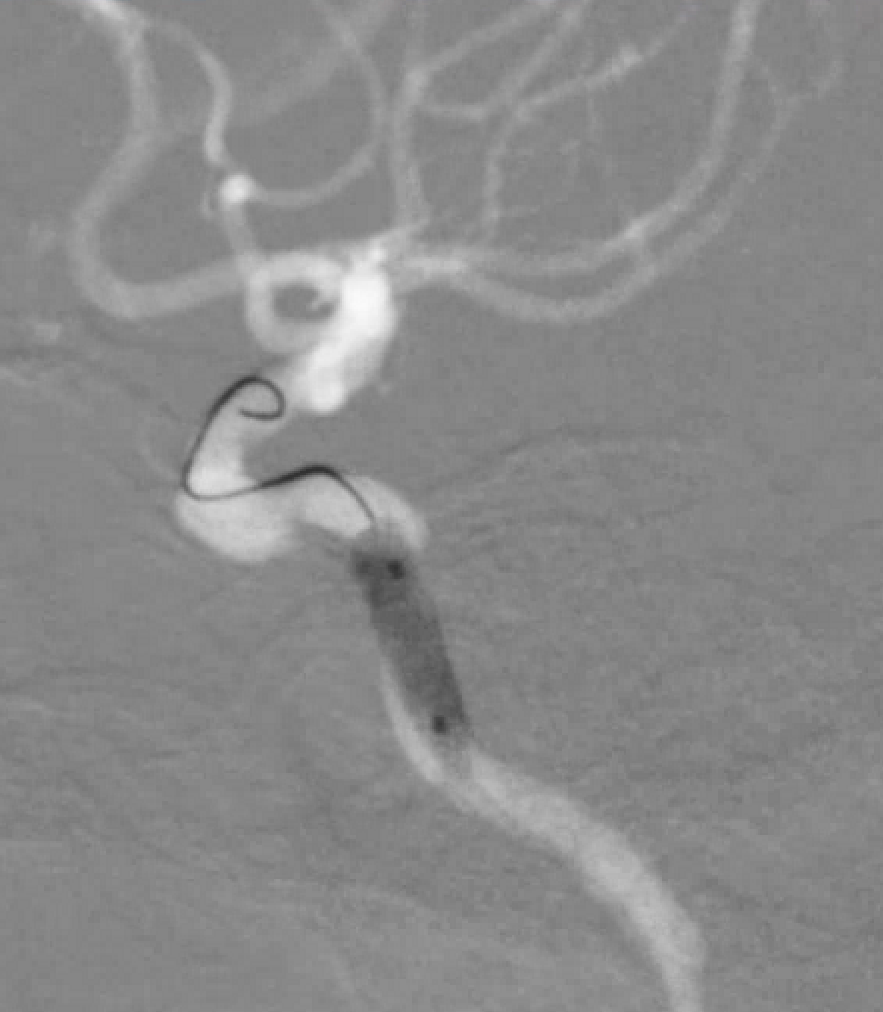

左侧瘤体形态欠规则,4mm×30mm Streamline 优先处理左侧动脉瘤

术后3月复查,瘤体未见显影,载瘤动脉通畅

同期4mm×20mm Streamline 进一步处理右侧动脉瘤